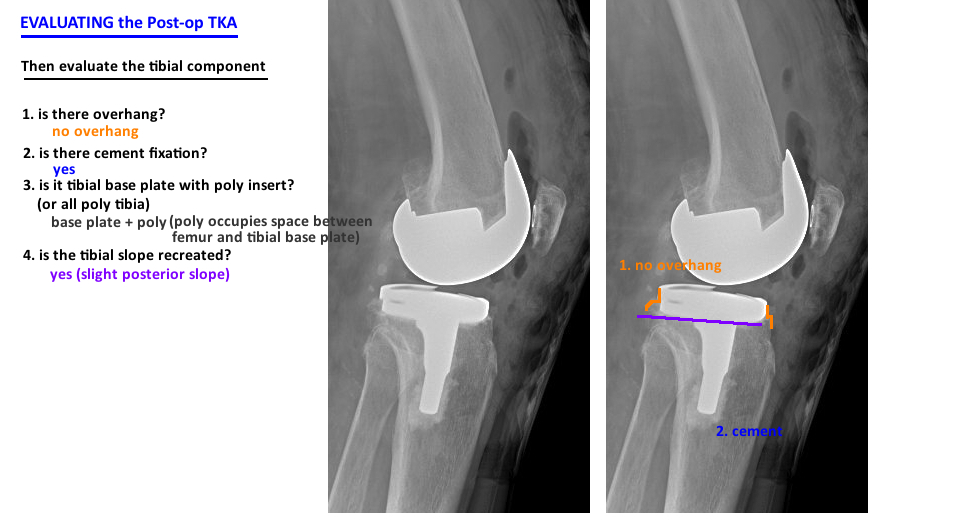

postop total knee arthroplasty lateral xr evaluation

tka post-operative xray assessment